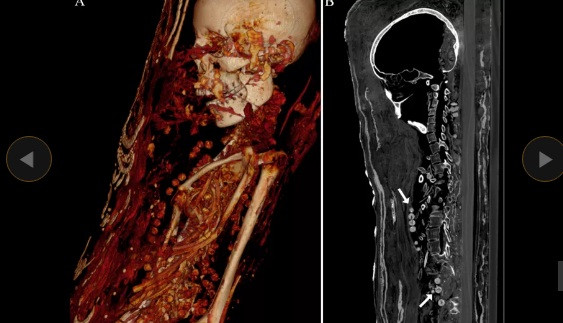

Các chuyên gia mới công bố thông tin đáng chú ý về 2 xác ướp được khai quật trong một ngôi mộ tại khu nghĩa địa cổ Saqqara, Ai Cập. Thay vì được đặt trong quan tài như nhiều trường hợp trước đó, hai xác ướp Ai Cập này được bảo quản theo cách đặc biệt.

Cụ thể, 2 xác ướp được quấn một lớp vải trước khi bao bọc bằng một lớp ván gỗ cực mỏng. Trên bề mặt của lớp ván gỗ là chân dung của người quá cố.

Chính vì vậy, các chuyên gia xem đây là những tấm vải liệm xác ướp đẹp nhất thế giới từng được phát hiện.

Thêm nữa, 2 xác ướp còn được trang trí bằng thạch cao và vàng. Nhà Ai Cập học Stephanie Zesch cho hay hai xác ướp gồm 1 nam và một nữ.

Kết quả kiểm tra cho thấy 2 xác ướp này qua đời vào khoảng năm 30 trước Công nguyên đến năm 395 sau Công nguyên.

Hai người này qua đời khi còn khá trẻ. Trong khi người đàn ông cao 1,64m qua đời khi khoảng 25 - 30 tuổi thì người phụ nữ có chiều cao 1,56m chết khi 30 - 40 tuổi.